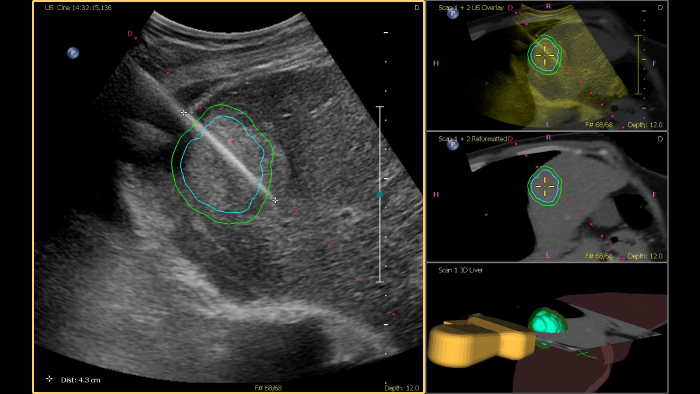

Os ecógrafos da Philips para a radiologia de intervenção suportam uma gama de capacidades sofisticadas para aplicações de intervenção. O fluxo de trabalho otimizado permite aos médicos alcançar uma fusão rápida e eficaz de TAC/RM/PET/CBCT com ecografia em tempo real, enquanto a navegação da agulha ajuda a orientar a biópsia e a ablação das lesões pequenas e de difícil acesso. A fusão e a navegação também podem ser utilizadas em conjunto com a ecografia com realce por contraste (CEUS), dando aos médicos acesso a ferramentas de diagnóstico ainda mais poderosas com visualização avançada.

O guia de biópsia CIVCO Verza pode ser ligado diretamente ao transdutor, sem suporte externo, permitindo a orientação da agulha com uma área cega mínima. Os sensores eletromagnéticos incorporados proporcionam uma solução ergonómica para fusão e navegação, não sendo necessários acessórios de acompanhamento externos.

Esta ferramenta semiautomatizada ajuda a delinear um contorno 3D à volta de uma estrutura de interesse, melhorando a orientação do procedimento mesmo em casos tecnicamente difíceis em que a lesão pode não ser visualmente óbvia ao nível de ultrassom. A lesão pode ser apresentada em 3D ou 2D através de uma modalidade complementar e sobreposta na ecografia ou TAC em tempo real, ajudando a visualizar a localização em relação às estruturas críticas circundantes.